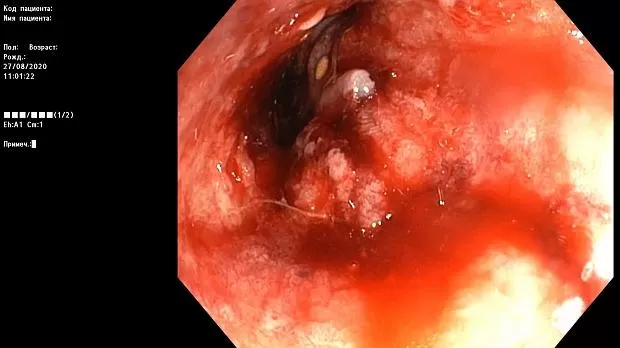

Краткое описание эндоскопической картины.

В проксимальной части сигмовидной кишки имеется асимметричное циркулярное сужение за счет плотной бугристой ткани, с признаками ригидности, структура поверхности и сосуды не визуализируются.

Просвет опухолевого канала 1 см, определенная протяженность — около 10 см. Патогистологическое исследование № 1455-62 от 28.08.2020 г.

Макроскопическое описание: Серовато — коричневых кусочков размером 0,1 — 0,2 см.

Микроскопическое описание: фрагменты представлены соединительнотканной стромой, в которой определяется рост криброзных и железистых структур, сформированных анаплазированным эпителием с крупными гиперхромными ядрами с выраженным полиморфизмом, отмечаются фигуры митозов; местами с поверхности кусочков сохранена выстилка типичным кишечным эпителием